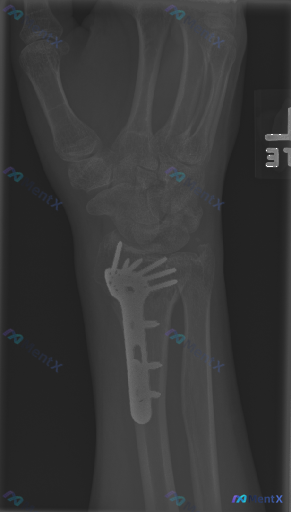

整理到一份左腕/前臂术后复查的影像资料,想和大家讨论一下判断思路。 基本情况 左侧桡骨远端骨折术后,本次为复查状态。 本次正位X光可见表现 1. 内固定装置:左侧桡骨远端有金属接骨板及多枚螺钉,位置覆盖骨折部位,形态完整,未见明显断裂或松动。 2. 骨折端:骨折线模糊,骨小梁结构基本连续,未见明确皮...